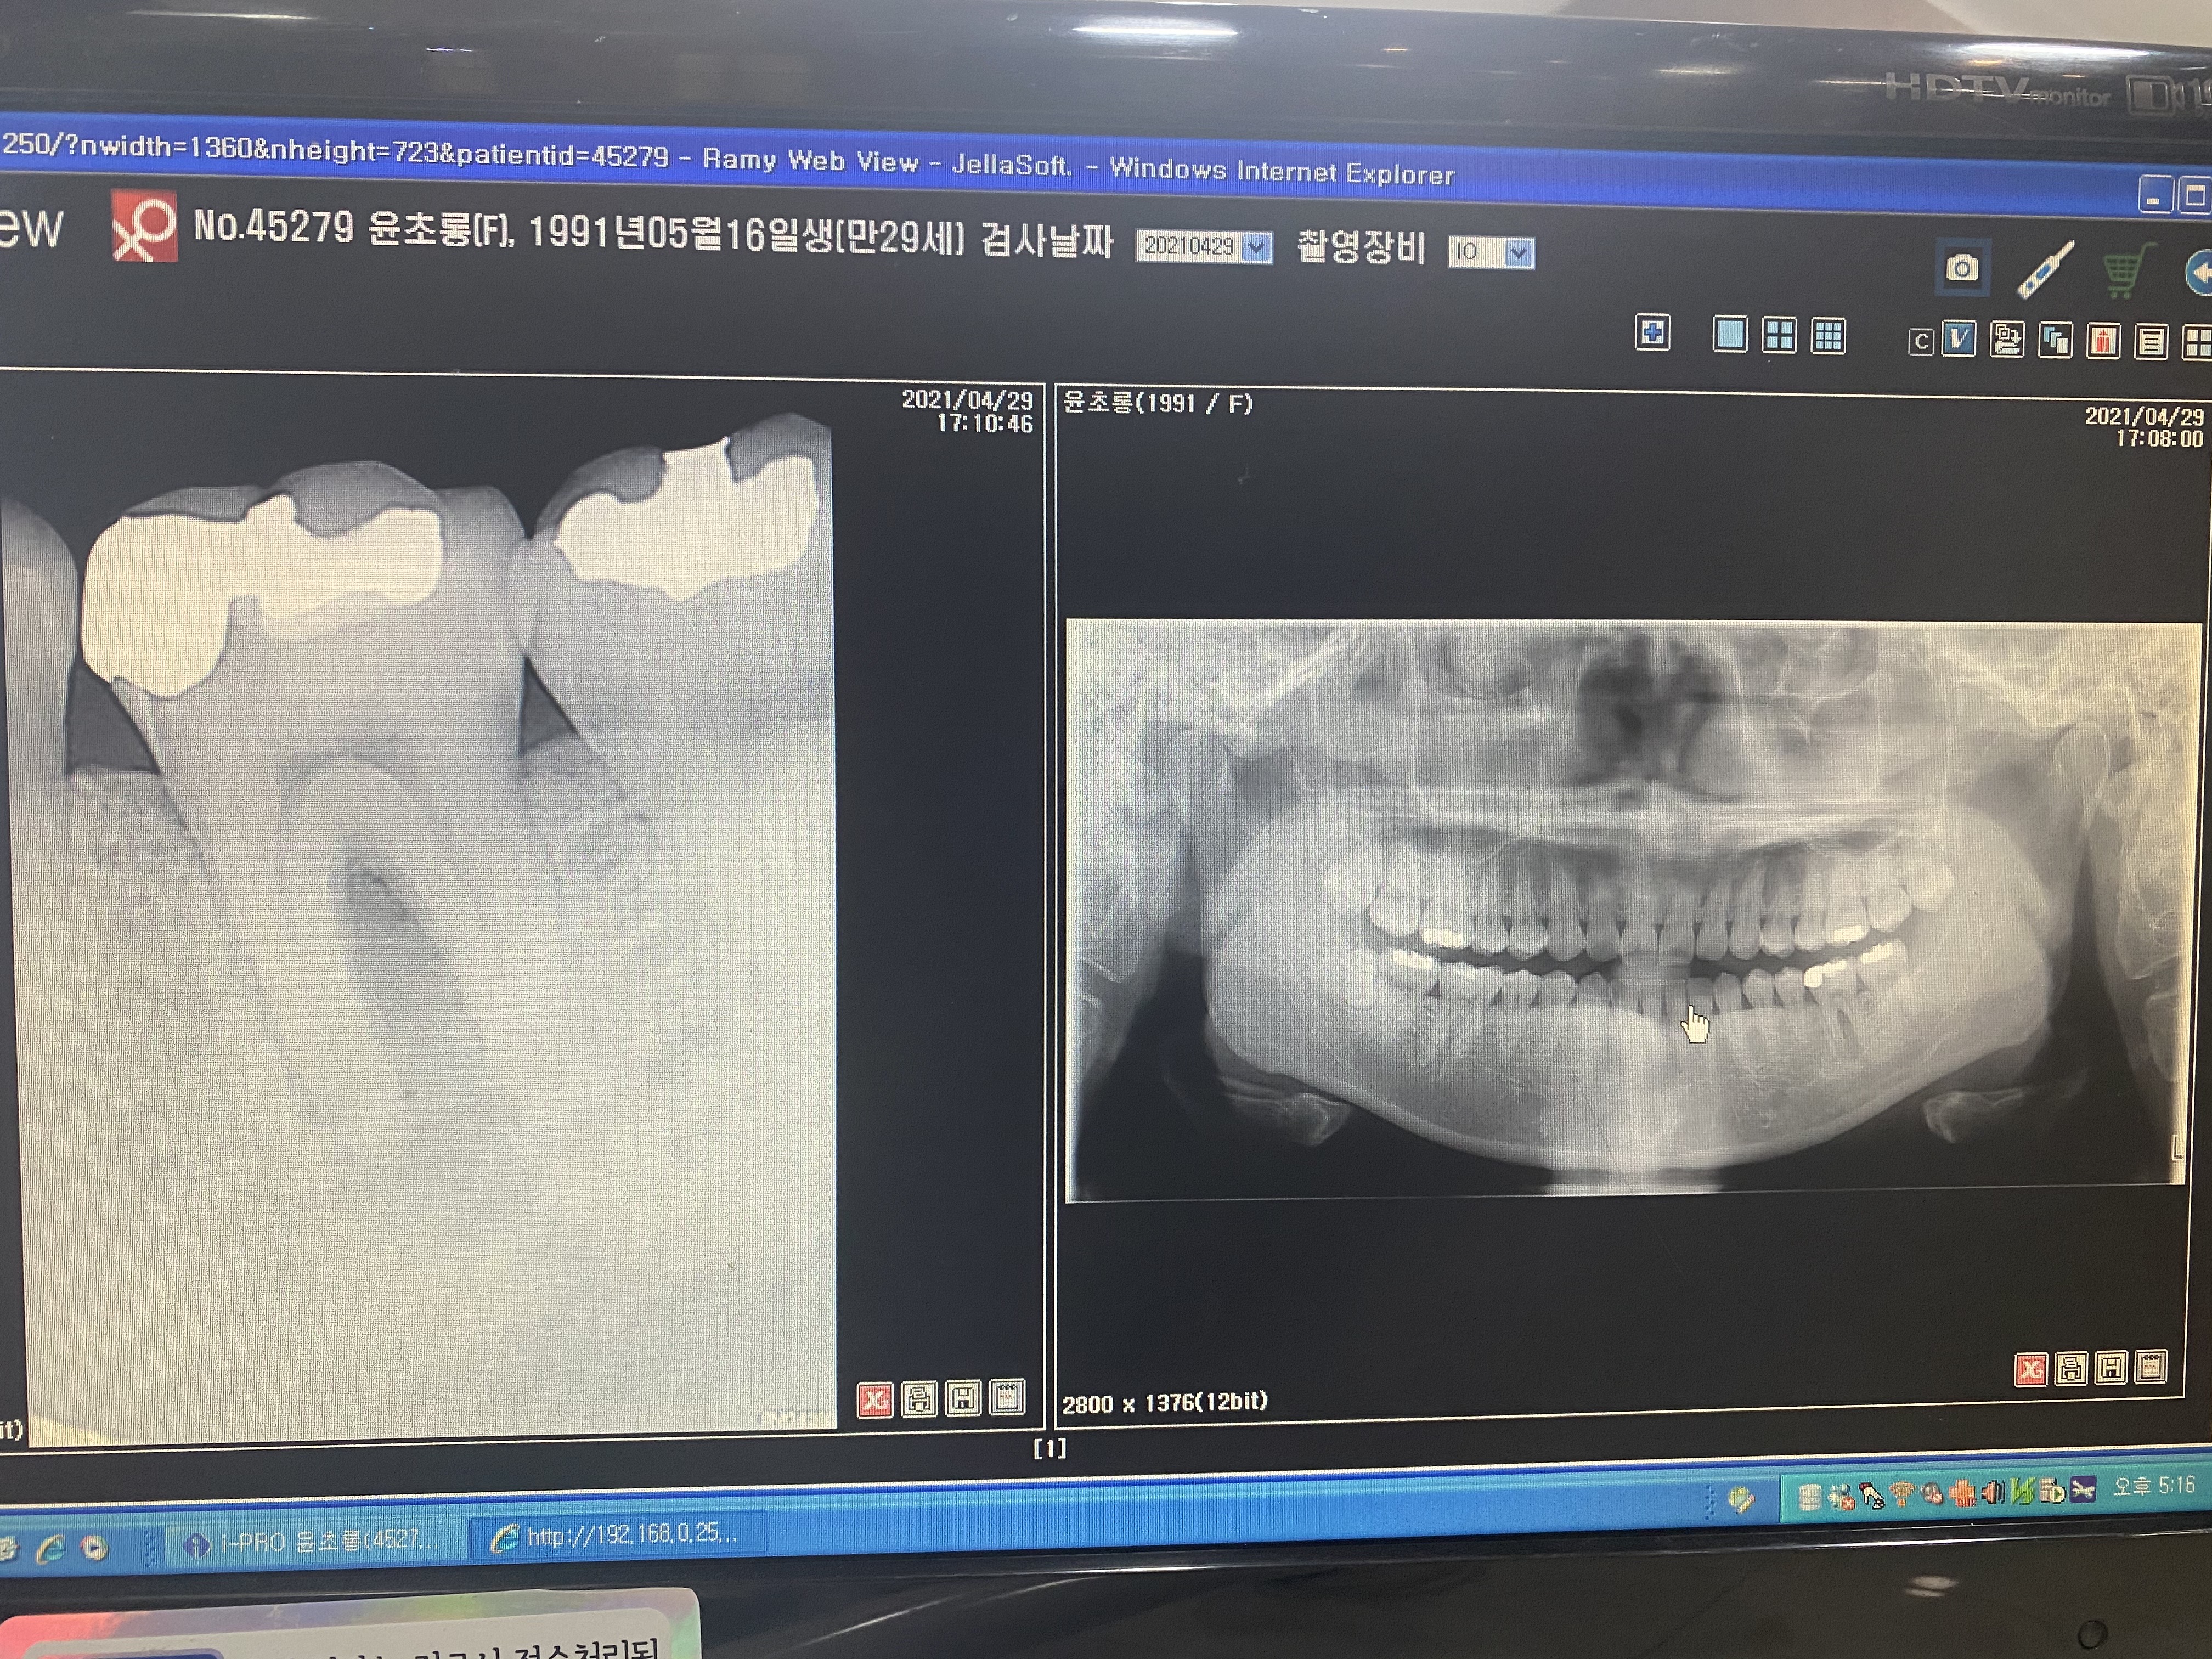

안녕하세요 선생님. 몇해전 선생님 조언으로 많은 도움을 받았었습니다. 이번에 가족이 통증이 있어 치과에 방문했는데 신경치료 또는 임플란트를 추천하더라고요. 제가보기에는 문제의 치아보면 치아부분에는 검게변하지 않아서 충치가 안보이는거 같은데 병원에서는 신경치료나 임플란트를 권하네요. 뿌리끝에도 검은 부분이 없는거 같고요. 뿌리사이에는 검게 염증이 보이는거 같습니다. 사진상으로 정확한 진단은 힘드시겠지만 조언좀 부탁드립니다. 2년전 선생님 말씀대로 신경치로안받고 저도 별다른 통증없이 잘 관리하면서 치아를 사용하고 있어서 항상 감사드립니다.

• 작성자hyuntae 작성자 본인 여부 작성자 | 작성시간 21.05.01 선생님 조언 감사드립니다. 염증이 심한건가요? 보통 검게 나오는게 염증으로 알고 있는데 사진상으로는 뿌리끝은 하얀거 같고 뿌리 사이가 검은거 같은데 그쪽이 염증이 심한건가요?